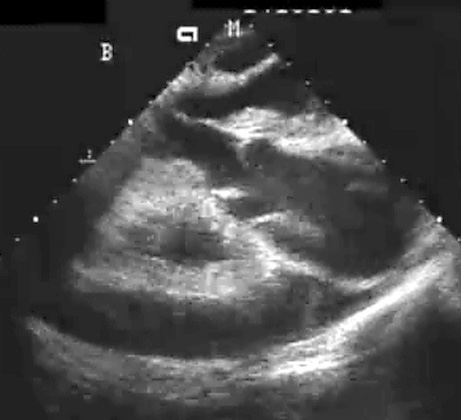

Echoacrdiogram

Describe what you see